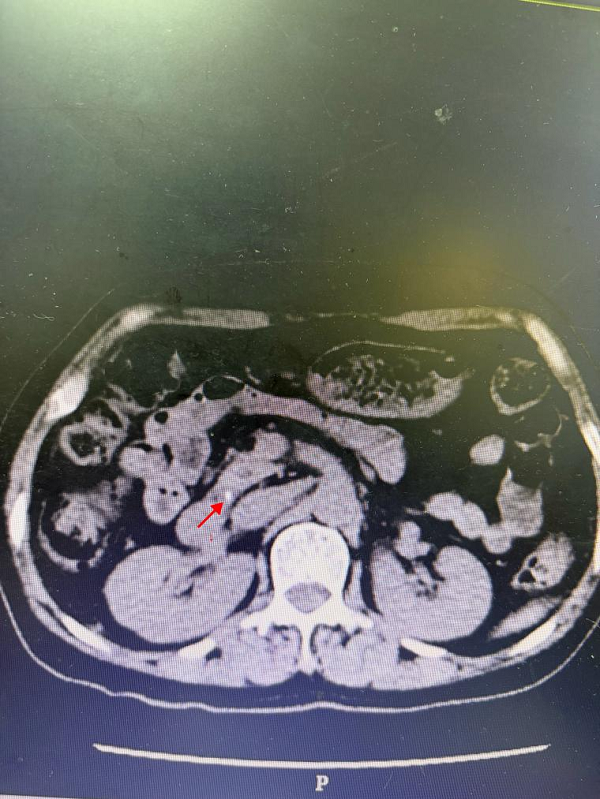

1. 内镜逆行胰胆管造影取石术:一名中老年女性患者,因“突发上腹部疼痛不适2天”入院。完善相关检查后诊断“胆总管末端小结石伴胆管炎”明确。考虑石头小,位置低,胆管扩张不明显,传统腹腔镜及开刀手术困难,家属要求保守1周后复查小石头仍位于胆总管末端,存在安全隐患。完善术前检查,经综合评估,由郭陵副主任医师、鲍慧文主治医师、汤如波医师组成的手术团队在静脉全麻下行内镜逆行胆管造影(ERC)术,保留奥狄氏括约肌功能,稍做扩张后取净小结石,留置鼻胆管引流管一根。患者术后无明显并发症,恢复顺利,术后2天出院。